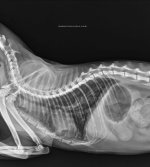

In early August, we got a repeat x-ray (attached) done which still showed bronchial lung pattern. She got Lasix and Penetrat (similar to Frenzyme). She stayed ok for about a month before symptoms returned.

I'm attaching her labs (Mar/Jul/Sep), x-rays (Aug/Sep/Nov/Dec) and 2d-echo (Dec).

1. Xray - RT LAT - Chiu - 08Aug2025.jpeg1.6 MB · Views: 41 -